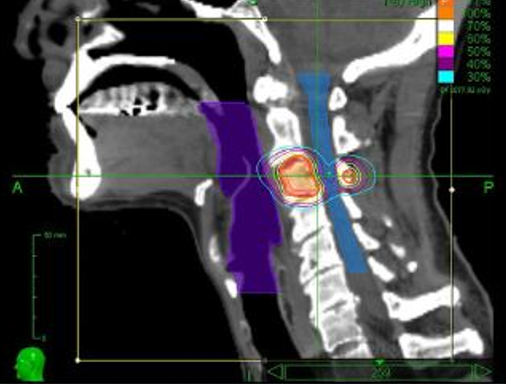

치료과정 x-ray 이미지

보조기구제작 및 치료 계획용 CT / MRI / 초음파 촬영

컴퓨터 치료 게획